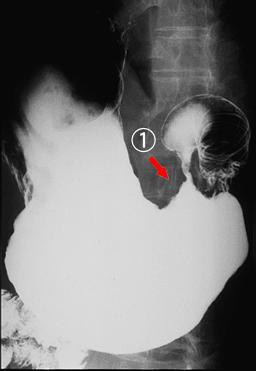

疾病(病理主体)的分类恶性淋巴系肿瘤/恶性淋巴瘤

部位(按器官分)胃(部位)/2个以上

检查方法X线

肿瘤最大直径40以上

肿瘤的深度sm